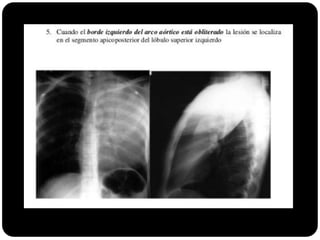

 Se borrar arco aórtico qual o segmento

afetado?

E agora?

 Apico posterior (LSE)